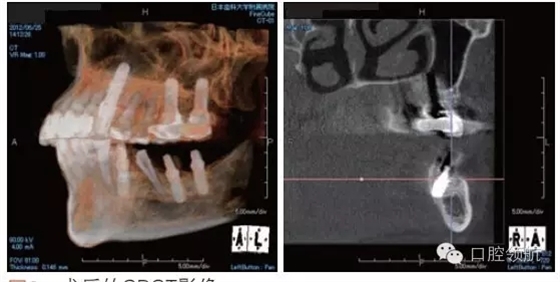

利用曲面斷層及CBCT檢查埋入部位情況,雖未出現(xiàn)與主訴相關(guān)的神經(jīng)損傷,但無(wú)意中卻發(fā)現(xiàn)了種植體的舌側(cè)穿孔(圖1、圖2)。

圖2 術(shù)后的CBCT影像。